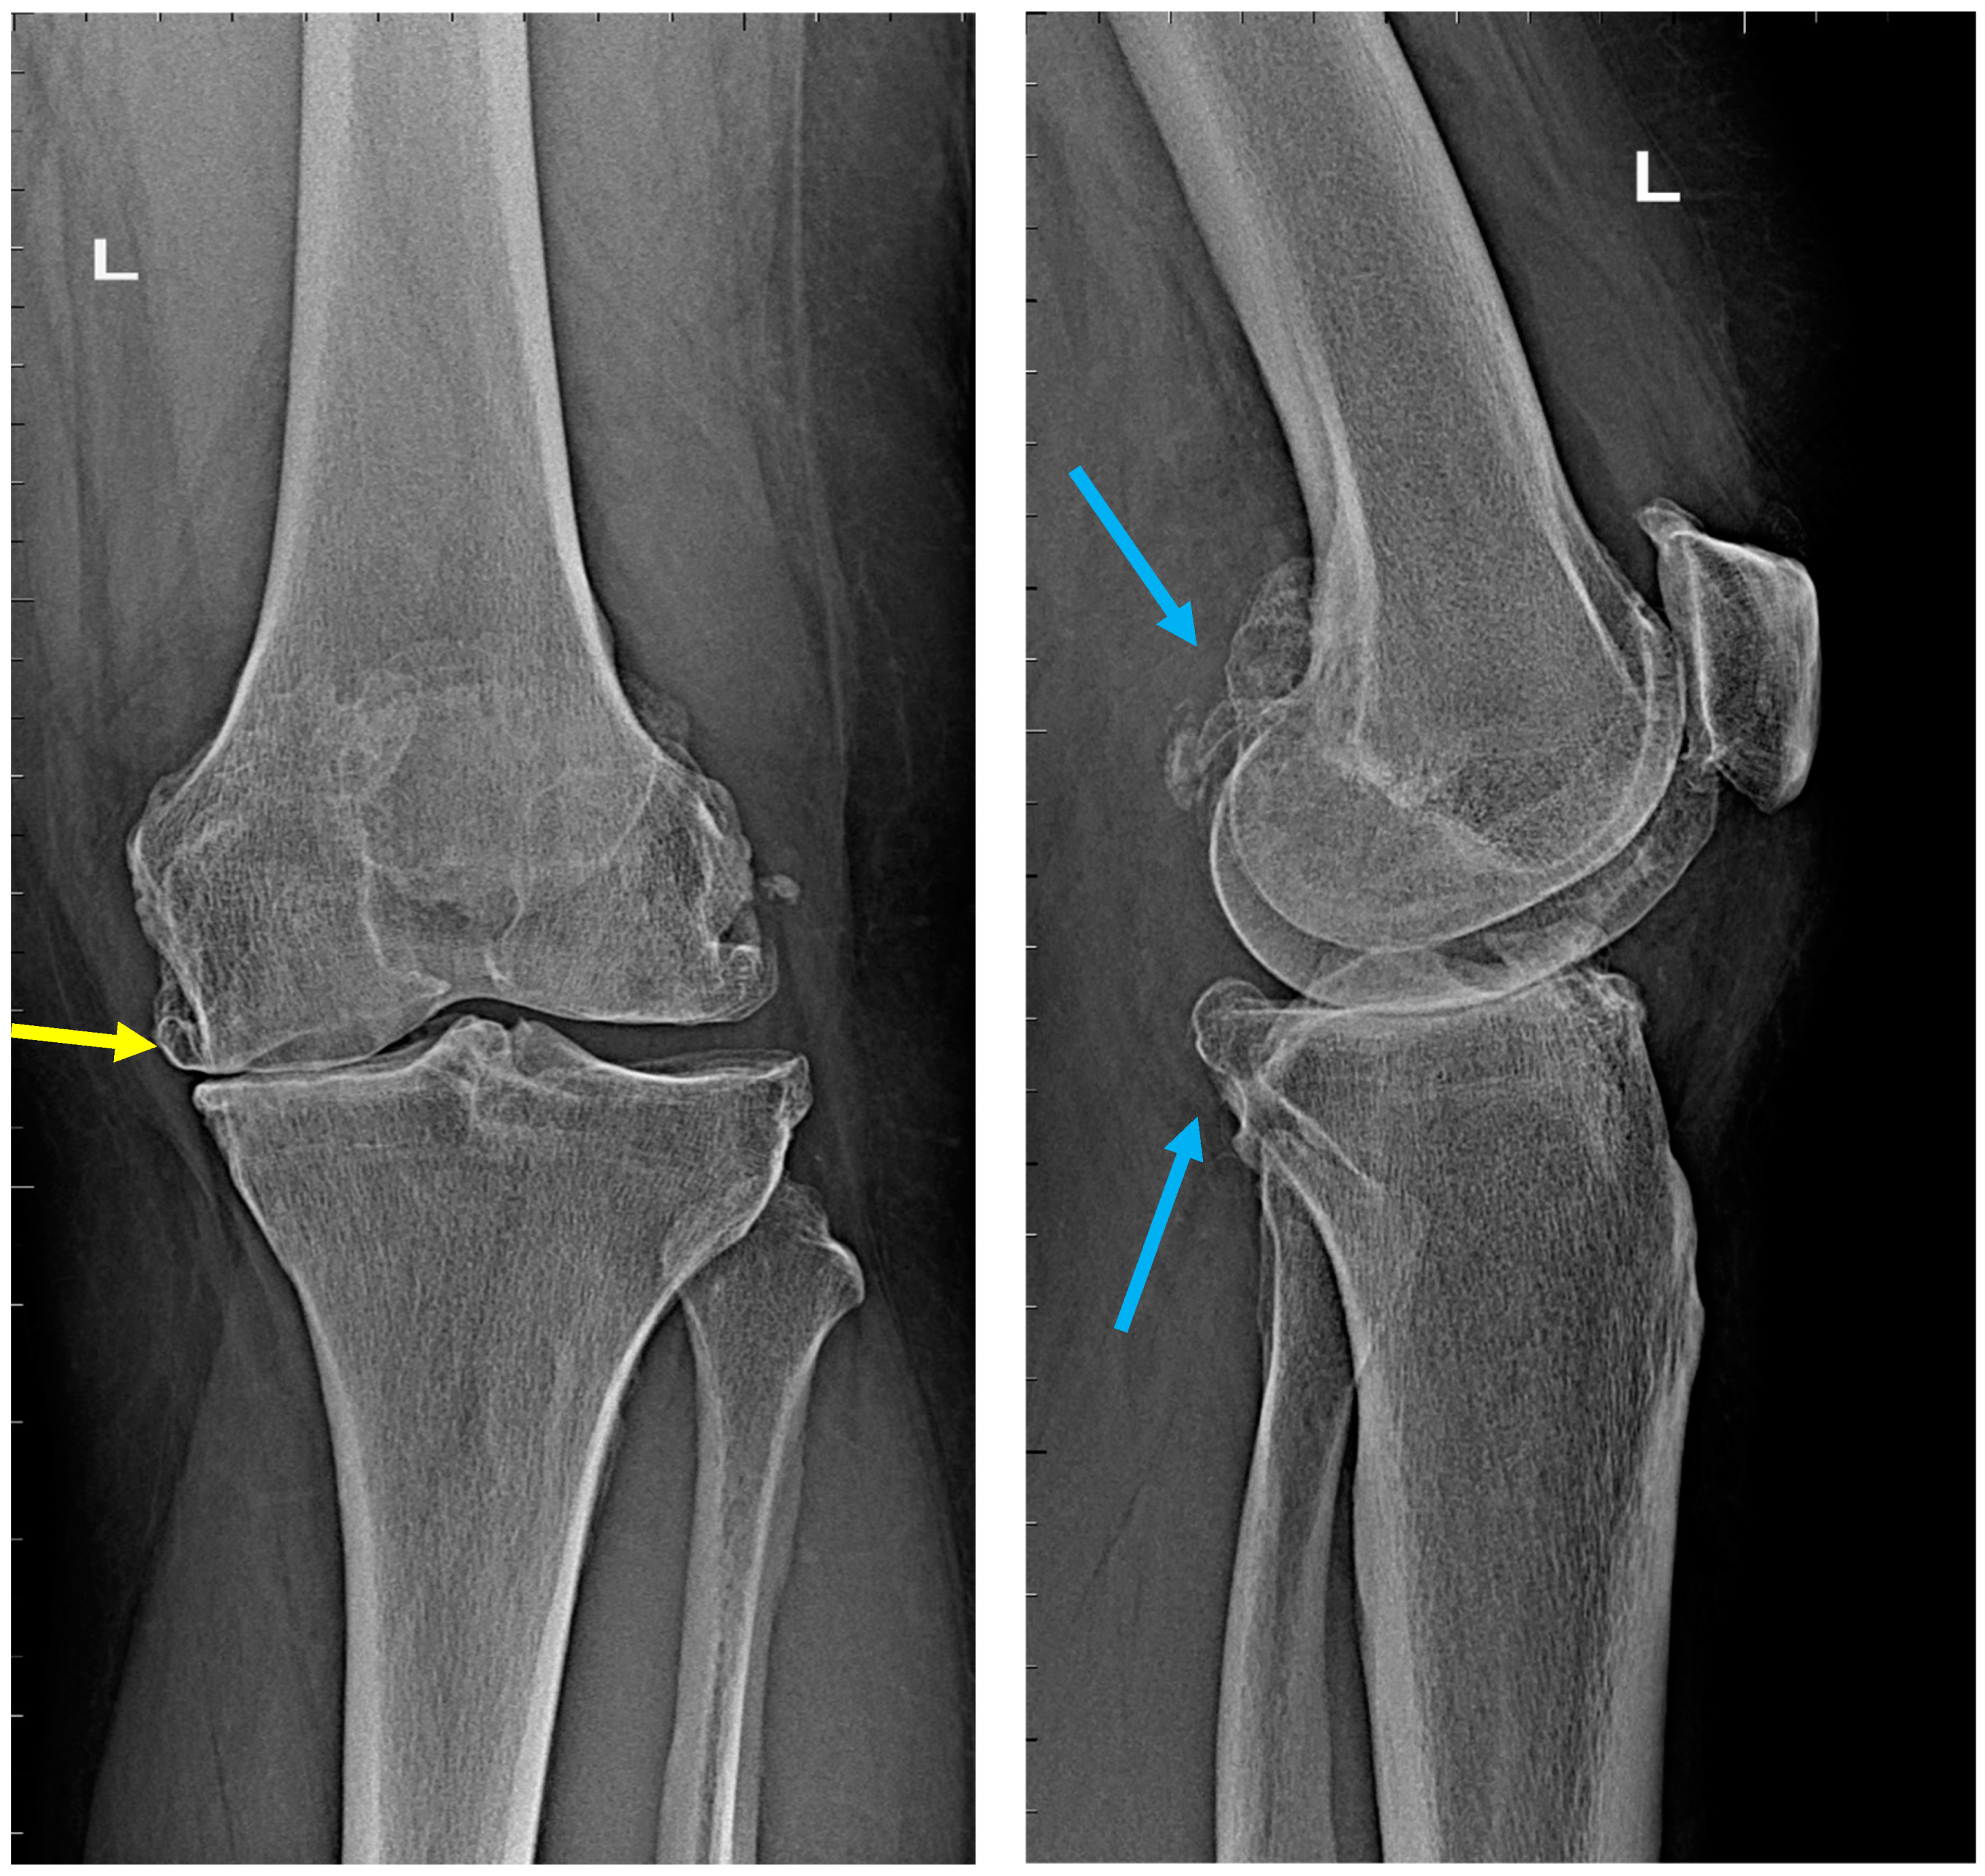

According to the classification of Kellgren, Lawrence, and Crofty-Lane, a classic X-ray examination, which is most often performed in anterior–posterior and lateral projections, defines the disease at the stage of advanced cartilage defects, which lead to secondary changes in the joint (Figure 2).

The patients underwent radiological assessment in accordance with generally accepted standards of radiological diagnostics. Based on the radiographs taken in the anterior–posterior and lateral positions, the severity of the osteoarthritis was determined on the Kellgren–Lawrence scales (Figure 3). On the first scale, patients were assigned to the appropriate degree of osteoarthritis, from grade 0 to 4.

Figure 3. Radiographs of the knee joint. Grade-4 arthrosis on the K–L scale, grade 3 on the Crofty-Lane scale. Left—AP view, right—lateral view. Visible (yellow arrow) complete narrowing of the joint space in the medial compartment, numerous osteophytes (blue arrows), and joint-axis disorders. Upper part: femoral bone, lower part: tibia and fibula. Source: proprietary material.